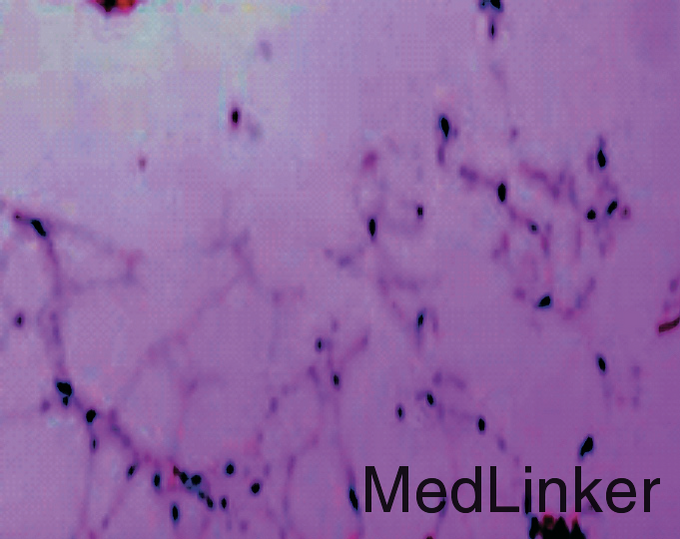

男,15岁,右踝部间断疼痛2年,加重伴右踝部肿胀1周。查体:右外踝上6cm处略肿胀,局部皮温正常,未触及包块,局部压痛明显,右踝关节活动度基本正常。右胫腓骨正侧位平片(图1):右腓骨远端干骺端膨胀性骨破坏,骨密度减低,骨皮质变薄,病灶内有分房,未见骨膜反应及周围软组织影。胫骨中下段髓腔内可见类圆形影,边界清楚,骨皮质无破坏。右踝MRI示:腓骨下段髓腔内显示4.5cm×2cm等T1、短T2异常信号灶,边界清楚,信号不均,其内可见分隔,病灶呈膨胀性生长,骨皮质变薄(图2)。右胫骨中下段髓腔内显示3.7cm×1.7cm椭圆形长T1、T2信号灶,边界清楚,信号均匀,边缘规则,骨皮质连续。结合病史及影像学表现考虑为良性病变,遂在硬膜外麻醉下行右腓骨远端病灶刮除、异体骨植骨、内固定术,右胫骨病灶刮除术。术后病理报告:(1)右腓骨远端髓腔内有5cm×4.5cm×1.3cm肿块。镜下见大片的梭形细胞伴有较多体积较大的多核巨细胞,局部见新生的骨小梁样结构,结合临床,考虑为GCT(图4)。(2)右胫骨远端髓腔内见灰黄色结节肿物,总体积3.5cm×3cm×1cm,镜下显示成熟的脂肪细胞并见增生小血管,结合临床考虑血管脂肪瘤(图5)。术后2周切口愈合良好,无红肿渗出现象,术后3个月患肢行走步态接近正常。术后10个月X线片见腓骨植骨融合,无明显骨破坏,胫骨开窗处可见骨修复(图6)。